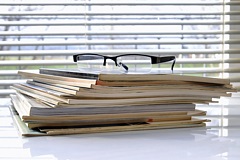

A beteg, 53 éves, fellebbezést nyújtott be a radiológiai klinikán panaszok megjelent három héttel ezelőtt, egy csomót a jobb kulcscsont feletti régióban. Nézve a jobb oldali supraclavicularis tapintható szilárd konzisztenciájú mozgásszegény képződése körülbelül 3 cm átmérőjű, feltételezett tumor folyamat. Held tűbiopszia citológia. Az így kapott anyagot talált sejtek mirigyes rák. Ismételt klinikai vizsgálat kimutatta, csomóponti oktatás a jobb pajzsmirigy lebeny. A feltételezett diagnózis „pajzsmirigyrák áttétekkel a supraclavicularis nyirokcsomó” célja, hogy a beteg ultrahangvizsgálat a pajzsmirigy. Amikor ultrahang pajzsmirigy nem nőtt mérete - 15 ml térfogatú a vozrostnoy sebességgel, hogy 19 ml. A kontúrok a prosztata sima, szimmetrikus részesedése. A háttérben egy homogén, finomszemcsés, átlagos parenchimális echogenicitása a jobb lebeny a nyúlvány határozza meg a folyadék, amely a kialakulását 15x10 mm. Képződése a belső kontúrja a láthatóvá izoehogennoe (viszonyítva a környező parenchyma) szilárd zárványok (ábra. 1).

Ábra. 1. A bal lebeny a pajzsmirigy térhatású obrazovniem.